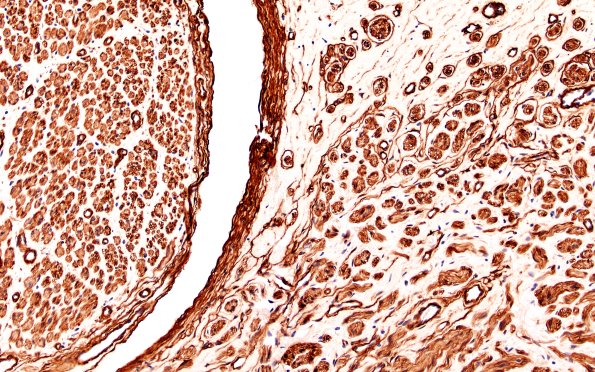

6D Neuroma (Case 6) PROX Coll IV 20X 1

This image shows the endoneurium on the left and the neuroma on the right. (Coll IV IHC)